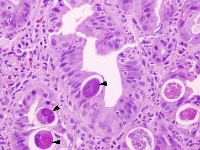

Qua hình ảnh ở trên, chúng ta có thể thấy được bệnh do giun lươn gây những tác hại như thế nào? [1] ấu trùng giun lươn đi xuyen da, niêm và có thể vào trực tiếp các mao mạch; [2] nhiễm ký sinh trùng lan tỏa trong máu; [3] từ mao mạch phổi đi đến các phế nang, đến khí quản, đến thực quản và ruột non và ròi trưởng thành, trong đó có giun cái và trứng cần quan tâm; [4] Trứng ra và díh trong niêm mạc, trưởng thành nên ấu trùng giai đoạn 1 và [5] bệnh có thể gây viêm phổi, đau bụng, rối loạn hấp thu, tổn thương niêm mạc ruột và tiêu chảy; chu trình tự nhiễm có thể gây khó chịu và viêm nhiễm tại chỗ hoặc toàn thân, lan tỏa đến các cơ quan ngoài tiêu hóa như phổi, gan, hệ thần kinh trung ương hoặc gây nhiễm trùng huyết.